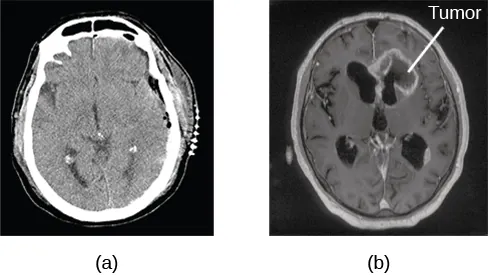

A computerized tomography (CT) scan involves taking a number of x-rays of a particular section of a person’s body or brain (Figure 3.26). The x-rays pass through tissues of different densities at different rates, allowing a computer to construct an overall image of the area of the body being scanned. A CT scan is often used to determine whether someone has a tumor, or significant brain atrophy.

Image (a) shows a brain scan where the brain matter’s appearance is fairly uniform. Image (b) shows a section of the brain that looks different from the surrounding tissue and is labeled “tumor.”

Figure 3.26 A CT scan can be used to show brain tumors. (a) The image on the left shows a healthy brain, whereas (b) the image on the right indicates a brain tumor in the left frontal lobe. (credit a: modification of work by "Aceofhearts1968"/Wikimedia Commons; credit b: modification of work by Roland Schmitt et al)